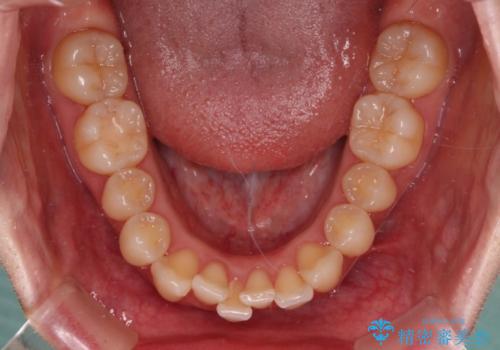

舌の突出癖がなかなか改善されず、上下前歯の接触がやや甘い状態での仕上がりとなりました。

接触が甘い場合、上顎前歯の叢生が後戻りを起こしやすくなるため、治療終了後の保定期間でも舌のトレーニングを継続するように指示しています。